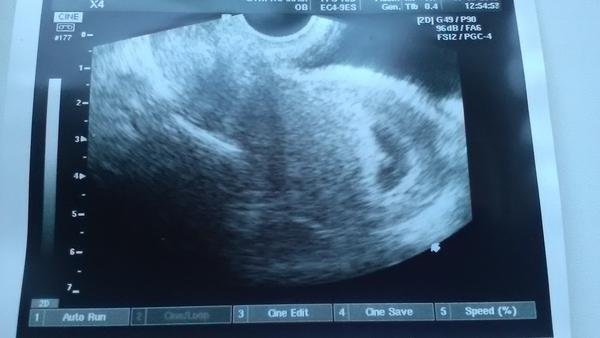

Těhotenský test. Dávám fotku. Co myslíte?

Tak nevim ... ☹ Dávám fotku, skuste posoudit...